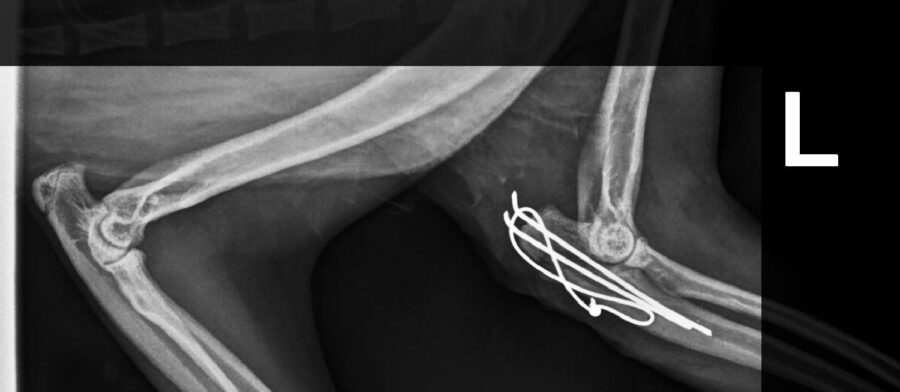

• Fracturen met platen, schroeven of pinnen